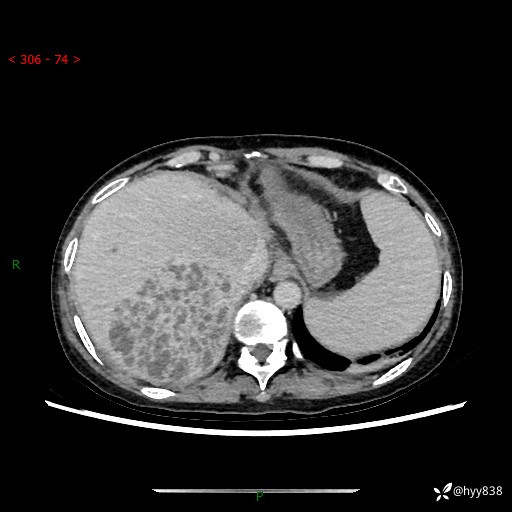

病例老年女性,发热来诊。如此“蜂窝煤”,治疗很棘手---结果公布~

性别:女

年龄:53岁

简要病史:发热(门诊急诊患者)

上腹部CT平扫